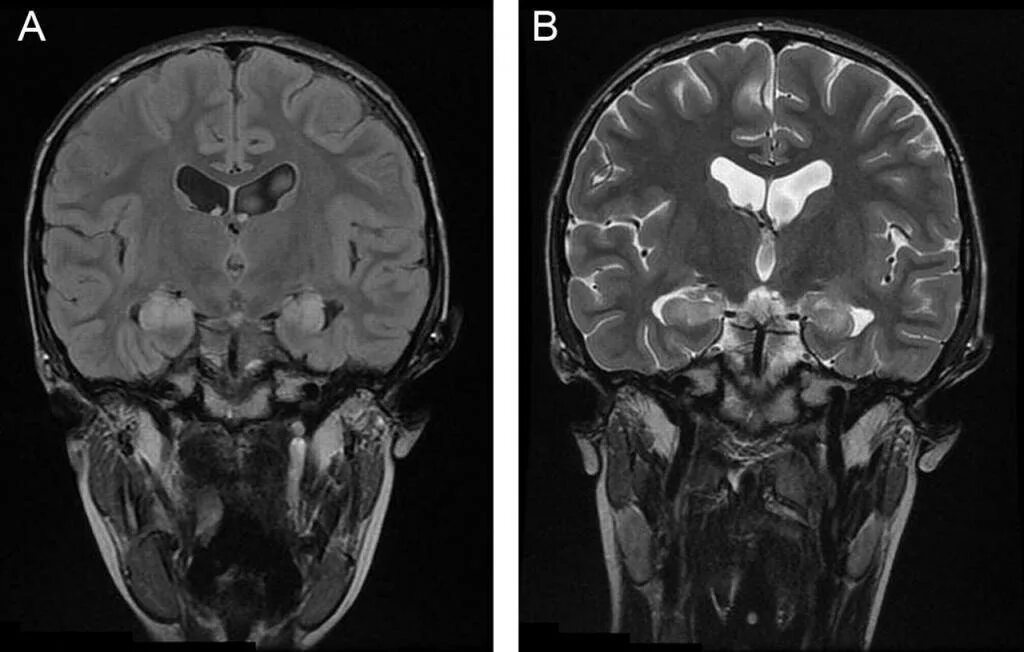

Мрт симптомы